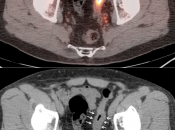

- Beware the small rectal cancer! As the ano-rectal region frequently demonstrates intense physiologic uptake, it is very easy to overlook a rectal malignancy, especially if it is an incidental finding. To avoid this error, always evaluate the rectum carefully on the sagittal whole body images. It is shocking to see how readily apparent a rectal cancer can be on these images, yet so easily overlooked in the axial plane.

- Always evaluate the colonic anastomosis on a follow up exam, as it is a occasional site of recurrent disease.